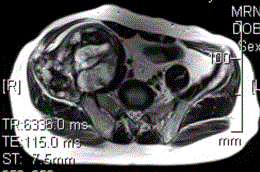

患者男,28岁,右下腹及臀部疼痛5个月余。查体:右髂骨外后侧压痛,右下腹可触及一软组织包块,质韧,固定。行骨盆正位CR、骨盆CT及MR扫描见下图。...

问题 患者男,28岁,右下腹及臀部疼痛5个月余。查体:右髂骨外后侧压痛,右下腹可触及一软组织包块,质韧,固定。行骨盆正位CR、骨盆CT及MR扫描见下图。 对于此病变的征象,描述不正确的是

选项 A.右髂骨翼分叶状溶骨性骨质破坏,边缘清晰硬化,形成巨大软组织肿块 B.右髂骨软组织肿块侵犯右侧腰大肌 C.右髂骨软组织肿块推压右侧腰大肌 D.T2WI示病灶内多发囊状高信号影 E.病灶内可见多发T1、T2均呈低信号的条状影,提示为纤维分隔

答案 B